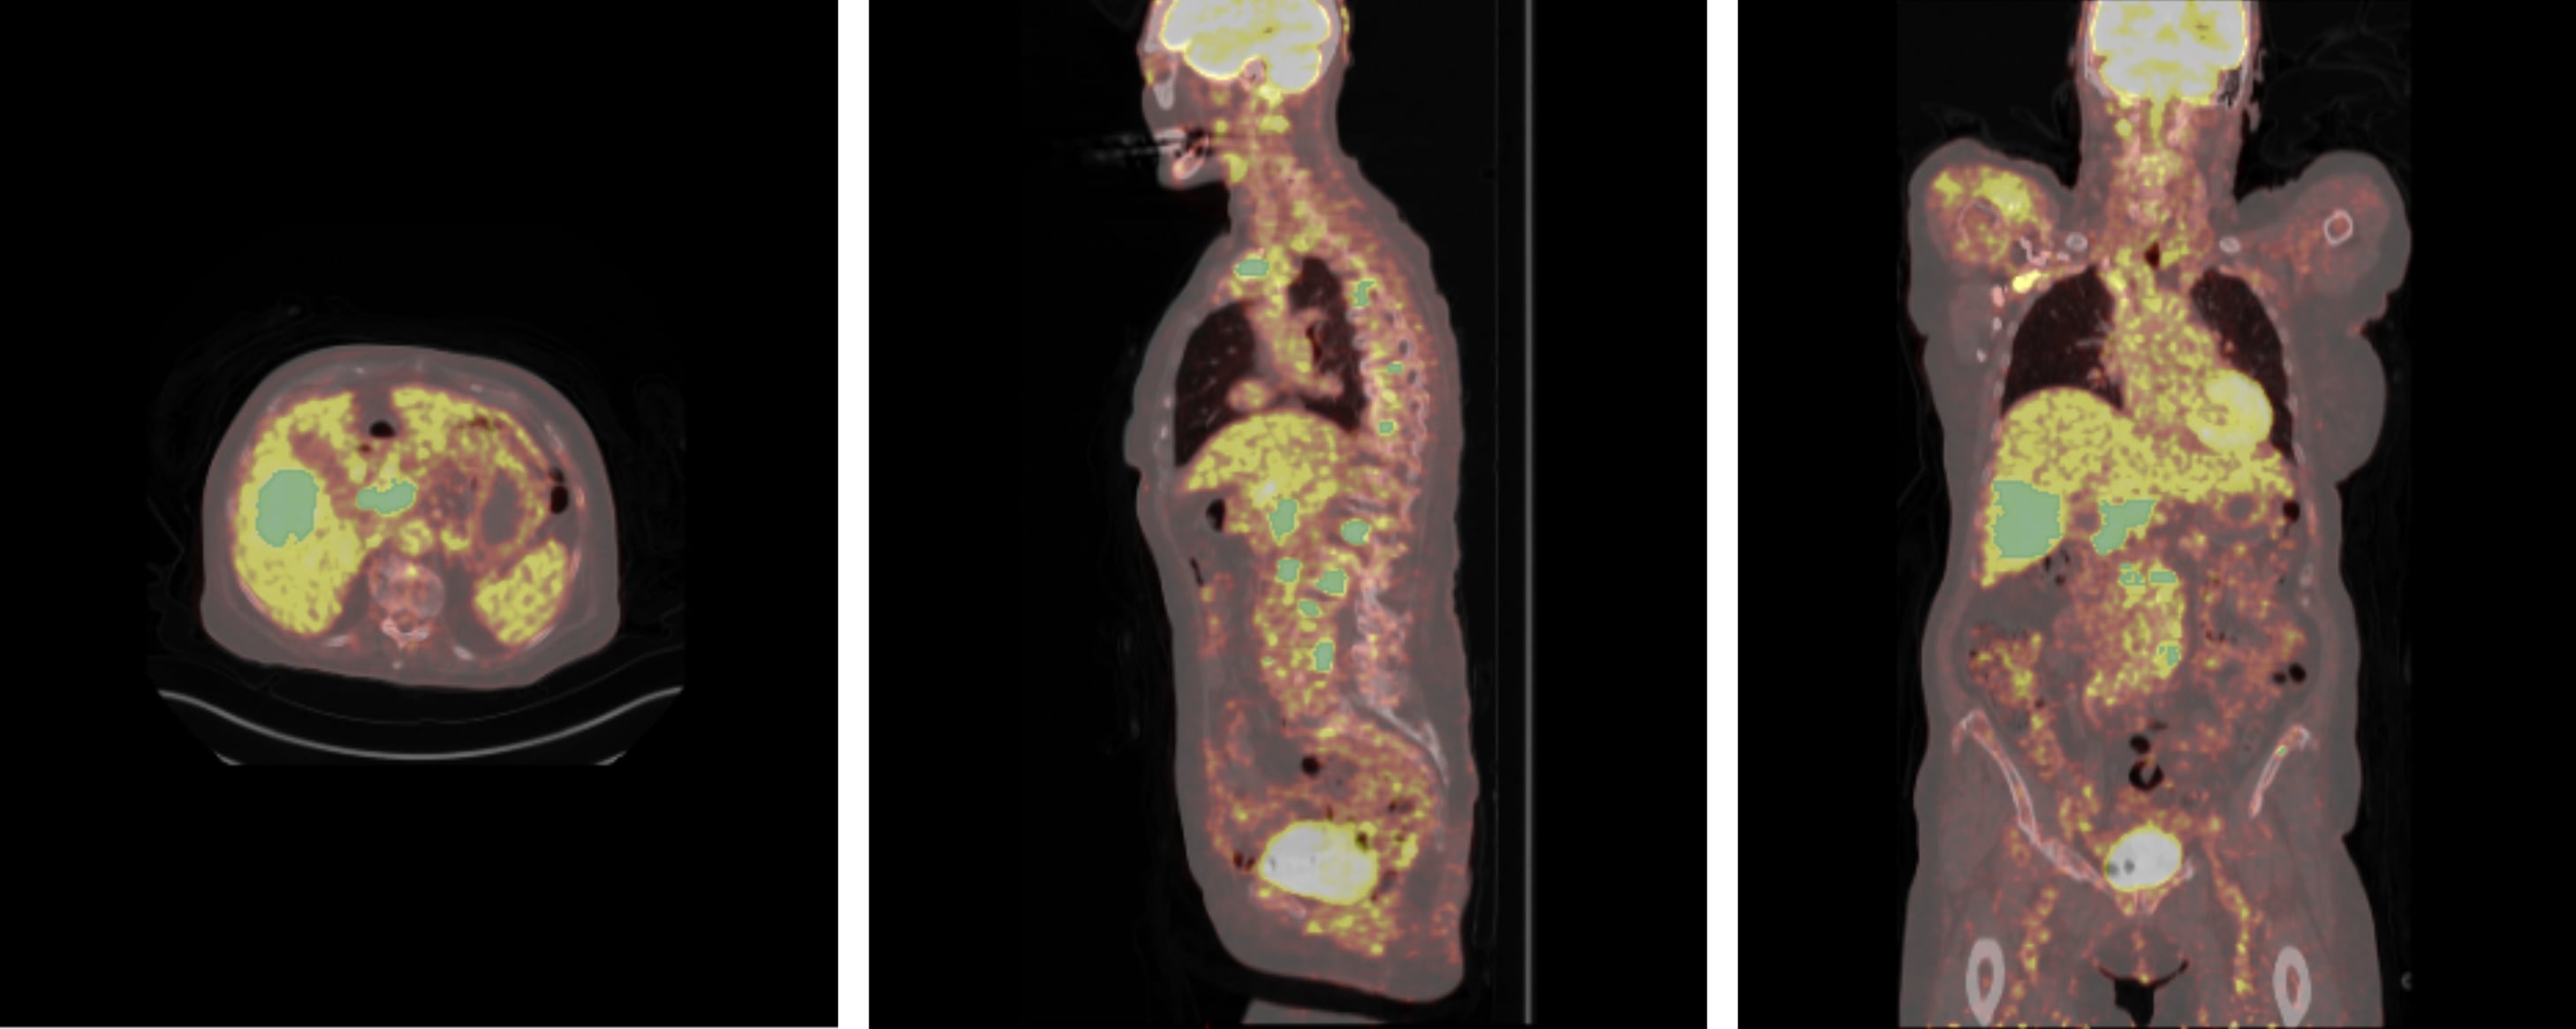

4.1.1 AutoPET Dataset

The first data set used in this study is the AutoPET dataset(autopet, autopetdata), This data set was used for the initial self-supervised pretraining stage of the Swin Transformer in our framework. The dataset comprises 1,611 whole body PET/CT scans (an example is shown in Figure 1). These include data from patients with histologically confirmed malignant melanoma (n=192), lymphoma (n=155), prostate carcinoma(n=332) or lung cancer (n=193), as well as a set of negative controls (n=739). PET acquisitions were performed using three different tracers: 597 prostate-specific membrane antigen ([18F]PSMA (n=369) or [68Ga]PSMA(n=228)) scans and 1,014 fluorodeoxyglucose ([18F]FDG).

Figure 1: PET/CT scan from the AutoPET Dataset, with manual annotations of Lymphoma lesions highlighted in green. From left to right: Axial, Coronal and Sagittal views.